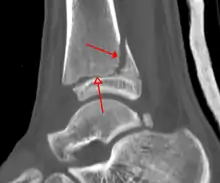

التصوير بالأشعة السينية

يمكن أن يظهر الكسر على الصورة السينية في الكعب الإنسي أو في الكعب الوحشي أو في الحافّة الأمامية أو الخلفية للجزء القاصي من الظنبوب. إذا تم كسر كل من الكعبين الوحشي والإنسي، يسمى ذلك بكسر الكعبين. إذا كُسر الكعب الخلفي أيضاً، يسمى ذلك بالكسر الكعبي الثلاثي.